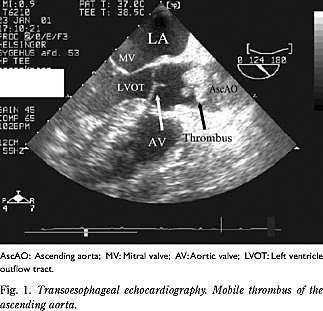

Patienten blev intuberet, og pga. de asymmetriske pulsforhold blev der foretaget TEE. Herved fandtes store, mobile trombemasser i aorta ascendens samt på overgangen mellem arcus aortae og aorta descendens, hvorfor man havde formodning om, at der var arterielle embolier til venstresidige ekstremiteter og cerebrum (Fig. 1 ).

Patienten blev overflyttet til kardiologisk specialafdeling mhp. karkirurgisk vurdering og evt. trombolyse. CT af thorax kunne bekræfte fundet af tromber i aorta, og CT af cerebrum viste et stort venstresidigt cerebralt infarkt, der omfattede pons. Ved den karkirurgiske vurdering konkluderede man, at patienten havde arterielle embolier i alle fire ekstremiteter, og at der ikke var mulighed for kirurgisk behandling. Yderligere behandling blev vurderet at være udsigtsløs, og patienten døde efter få timer.